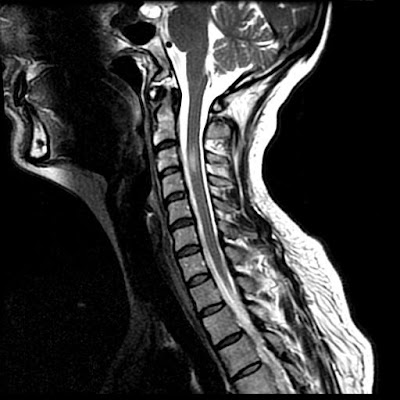

Findings

These MR images demonstrate focal anterior displacement of the spinal in the mid thoracic spine. The cord (Images 1,2 and 3) appears to be either tethered anteriorly or compressed from the posterior aspect. The intradural space behind the cord is widened and has signal characteristics identical to CSF (Images 1,2 and 3).

Diagnosis: Idiopathic Thoracic Cord Herniation

Spinal cord herniation occurs when the cord herniates through a defect in the dura mater. These dural defects are typically located anteriorly or laterally, and occur most often in the mid-thoracic region. They may be idiopathic, post-traumatic or iatrogenic related to prior spinal surgery. Some have suggested that a herniated and calcified disk may cause thinning, erosion, or rupture of the dura, which may also be secondary to congenital weakening of the ventral dural fibers. The presence of free flow of cerebral spinal fluid dorsal to the herniated cord is key to differentiating a spinal cord herniation from an arachnoid cyst. Spinal cord herniation occurs most commonly in the middle-aged. Symptoms of myelopathy including chronic leg pain, gait disturbance, incontinence, and leg weakness are commonly seen and may slowly worsen over time if left untreated. The most common clinical feature reported is the Brown-Séquard syndrome consisting of hemiplegia and contralateral temperature sensation deficits and pain.

Typical imaging findings are focal anterior displacement of the spinal cord with expansion of the dorsal subarachnoid space. The preferred imaging modality in the setting of myelopathy is MRI, which is often sufficient for making the correct diagnosis. Myelography with CT may be required in ambiguous cases and to demonstrate the exact location of the dural defect. With cord herniation, myelography reveals uninterrupted flow of contrast and the absence of a filling defect posterior to the herniated cord segment. An arachnoid cyst will present during myelography as an early filling defect posterior to the displaced cord. Contrast may fill the cyst with time, so rapid acquisition of CT-myelograpgy after the initial myelographic images is essential. Phase contrast cine MR imaging may provide similar CSF flow information, in addition to restricted cord motion.